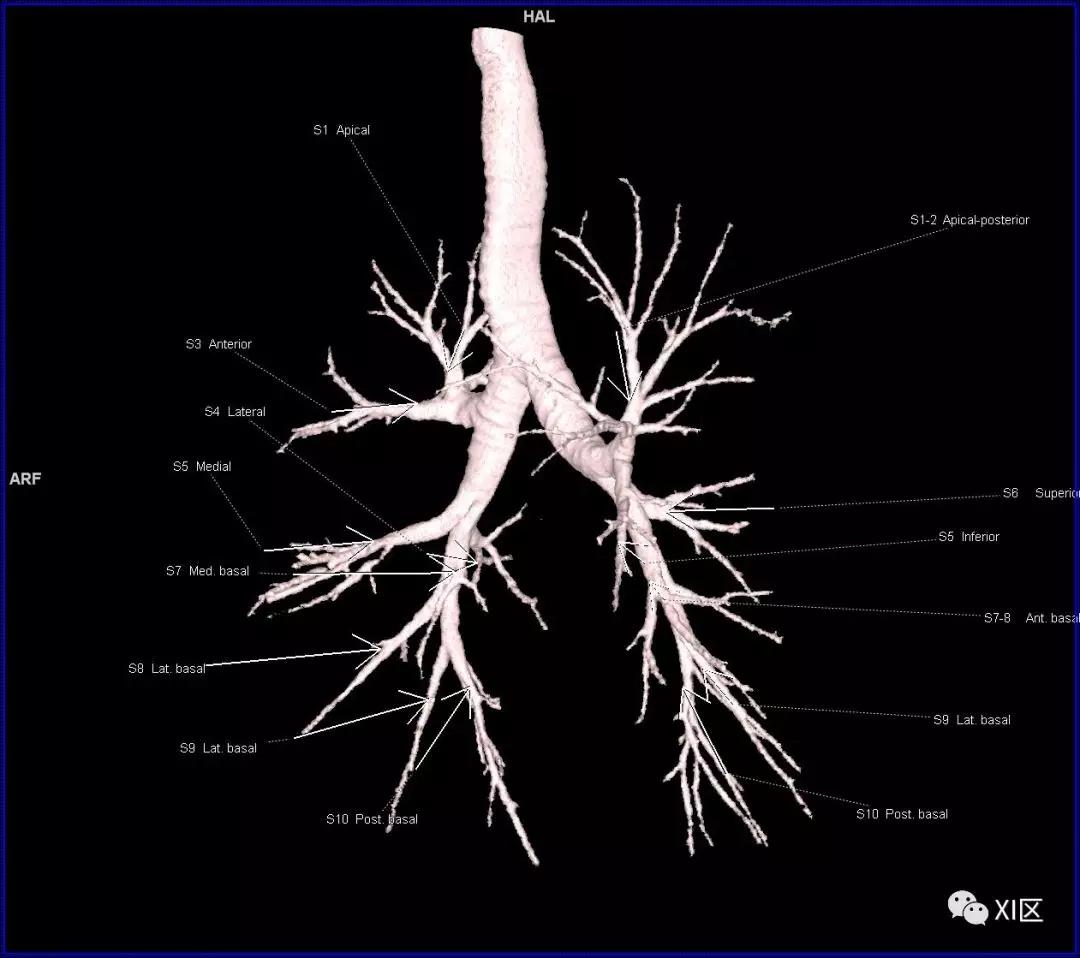

气管树的解剖

人的支气管(第1级)至肺泡约有24级分支。支气管经肺门入肺,分为叶支气管(第2级),右肺3支,左肺2支。叶支气管分为段支气管(第3~4级),左肺8支、右肺10支。段支气管就是肺的分段的依据。段支气管反复分支为小支气管(第5~10级),继而再分支为细支气管(第11~13级),细支气管又分支为终末细支气管(第14~16级)。从叶支气管至终末细支气管为肺内的导气部。终末细支气管以下的分支为肺的呼吸部,包括呼吸细支气管(第17~19级)、肺泡管(第20~22级)、肺泡囊(第23级)和肺泡(第24级)。

气管支气管形如树状,因此也称气管支气管树。

段支气管的命名(图片源自网络)

段支气管的命名